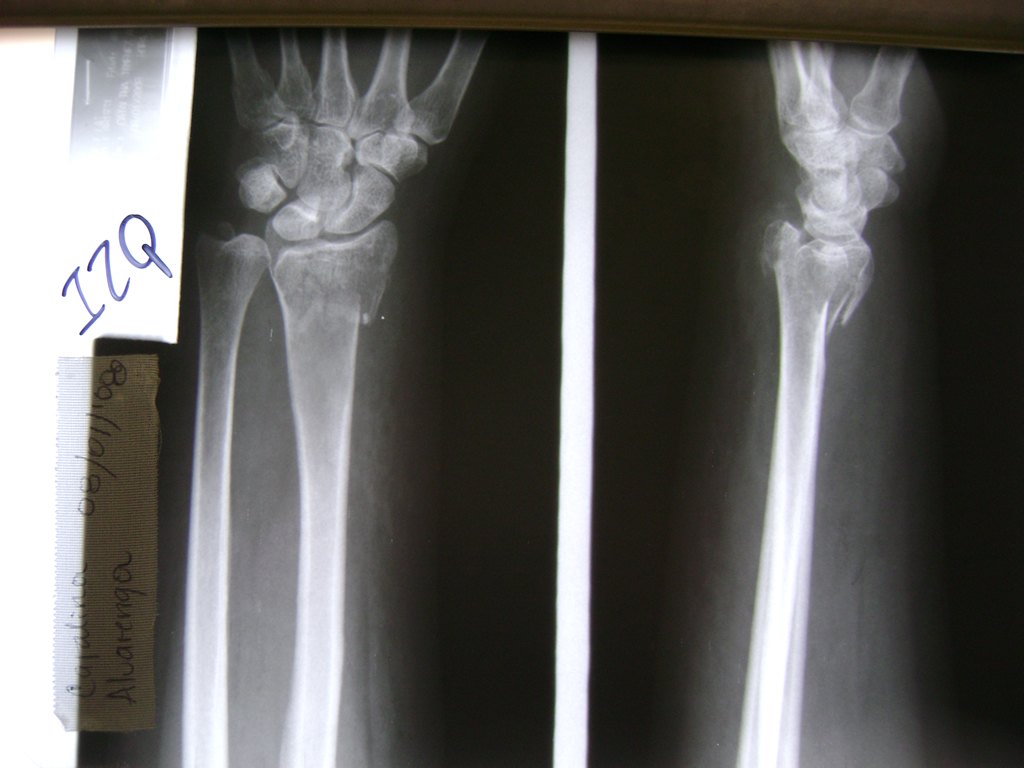

Los procedimientos más comunes en cirugía de la mano son aquellos destinados a reparar traumatismos, incluyendo lesiones de tendones, nervios, vasos sanguíneos, y articulaciones; huesos fracturados; y quemaduras, cortes, y otros daños de la piel.